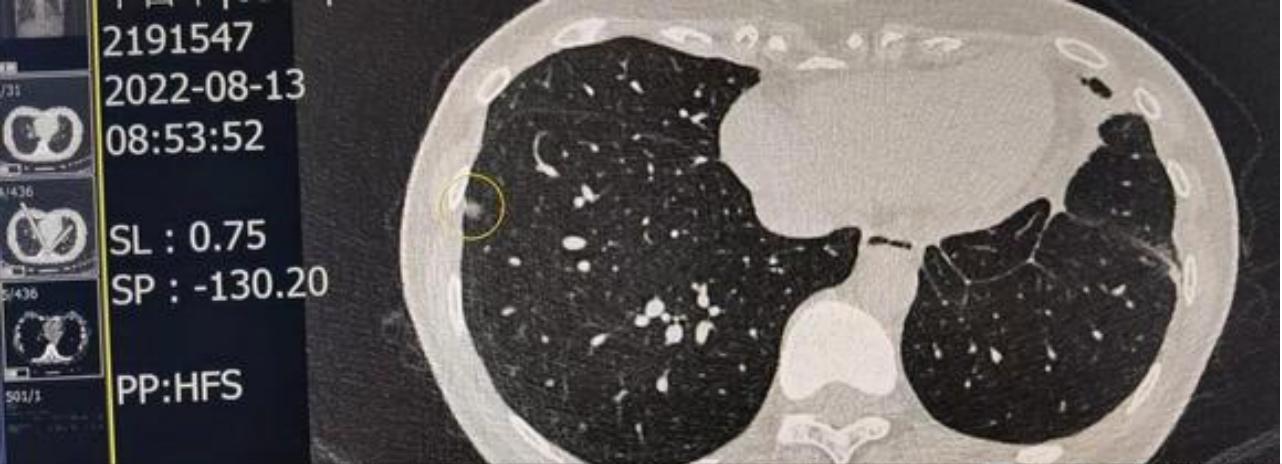

请戴主任解惑,我今年39岁,不抽烟,无高危粉尘环境,无不良嗜好;2021年10月体检发现双肺有3个磨玻璃结节,分别于2022年1月和9月在本地医院手术切除。术后病理结果为1个原位癌1个微侵润1个侵润,侵润的位置在右肺下叶,贴壁状生长为主的腺瘤,肿瘤大小1厘米*0.4厘米, 侵犯脏层胸膜,未见转移。基因检测19del突变。

术前CT(2022/8/13)